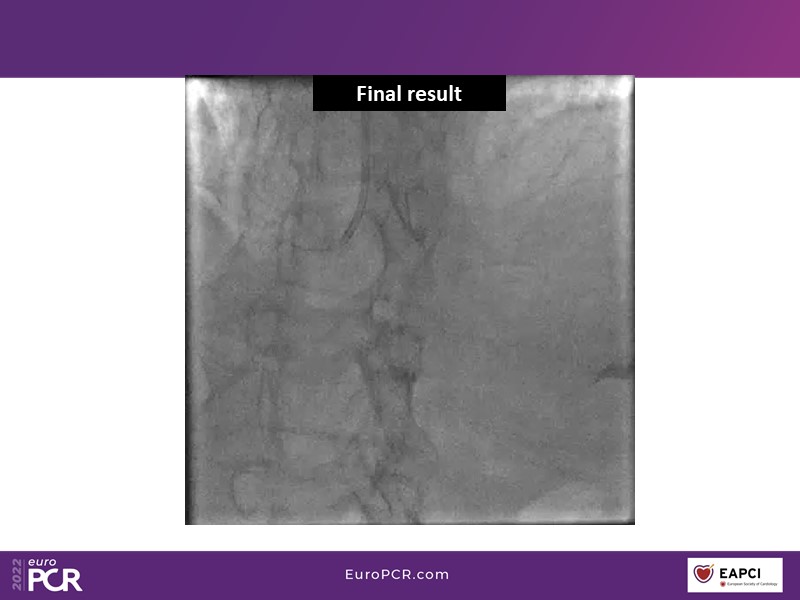

Alexandre Abizaid, Marco Valgimigli, Fazila Malik, Luca Testa, Patrick W. Serruys, Damiano Regazzoli, Kumar Prathap, and Sandeep Basavarajaiah take turns in this session to discuss two innovative technologies: a stent platform with nanotechnology and a novel drug-coated balloon (DCB). These novel technologies both have unique features that could change daily practice and improve outcomes.

- To find out more about the application and mechanism of a sirolimus coated balloon for coronary artery disease treatment with case presentations in complex settings

- To understand how useful is a DES and DCB stent platform in complex coronary artery disease settings with case demonstrations and follow-up in diabetes mellitus